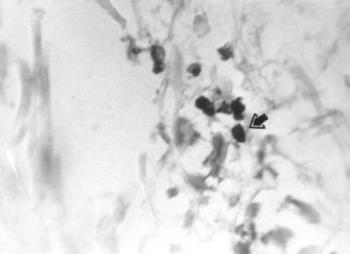

Weser és mtsai (1989) folyadék kromatográfiával 1200 éves múmia agymaradványaiból szuperoxid-dizmutáz aktivitást határoztak meg. Később (1994 és 1995) az alkalikus foszfatáz izoenzimeket kémiai és immunológiai eljárásokkal azonosították. Mindez előre vetítette, hogy némely fermentum mikroszkóposan is detektálható lesz. Tudomásunk szerint elsőként nekünk sikerült a vörösvértestek peroxidáz enzimét (17. ábra) egyiptomi múmia bőrében hisztokémiailag azonosítani (Józsa és Pap 1996). Hoyle és mtsai (1997) egyiptomi és perui múmiák perifériás idegeinek nitritoxid-szintetáz és neuropeptidáz enzimeit mutatták ki.

17. ábra. A vörösvértestek peroxidáz enzimaktivitása (nyíl) jól kimutatható a római kori múmia bőrvérzésében. Peroxidáz-DAB reakció. 400× nagyítás